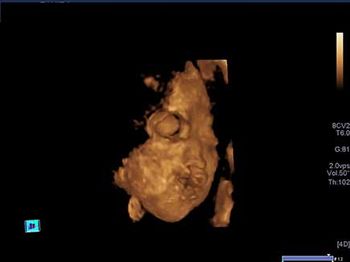

Challenge your anatomy knowledge; what body part is this 3-D image showing?